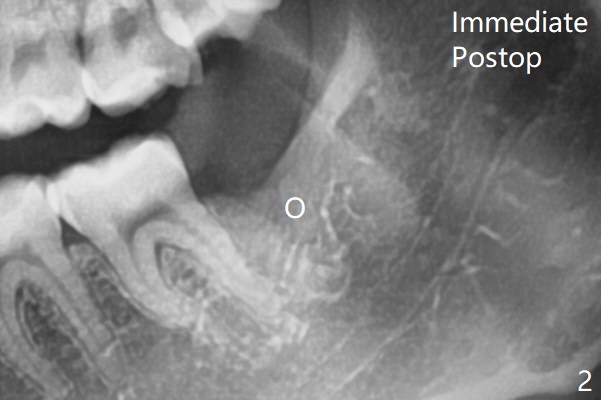

The tooth is removed with buccal trough and sectioning (avoiding mesial elevation as much as possible).  Osteogen plug is placed against the mesial wall of the socket (horizontal placement, Fig.2).